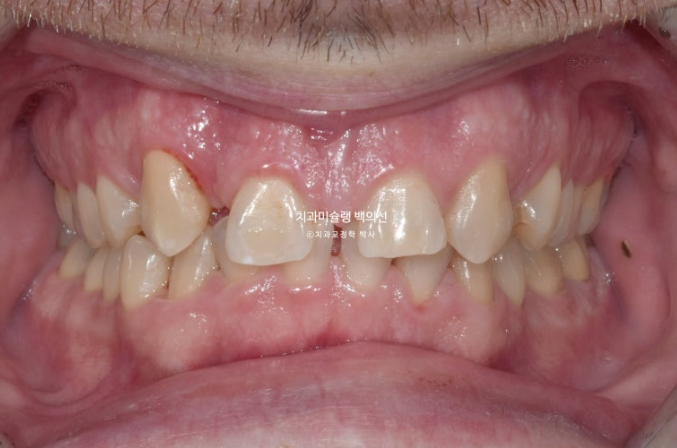

오늘은 부원장님 인비절라인 케이스를 보면서 앞니 2개가 선천적으로 없는 경우 (결손치) 인비절라인 교정 후 임플란트까지 치료 진행과정에 대해 보여드리겠습니다.

24년 1월 교정치료를 위해 내원한 외국인 환자분입니다.

23.01

위 앞니 4개중 2개가 없습니다. 앞니가 크게 벌어져 있고 아래 앞니가 위로 솟아 위 입천장 잇몸을 칠 정도의 심한 과개교합이 있습니다.

만약 이렇게 선천적 결손치아와 돌출입이 혼재한다면 결손치아를 발치한 셈 치고 벌어진 공간을 모으며 돌출을 해소하는 방향으로 치료를 하기도 합니다.

하지만 환자분은 전형적인 caucasian의 안모를 보입니다.

즉 입술이 얇고 콧대가 높고 턱끝이 튀어나와 앞니가 뒤로 더 들어가면 큰일날 상입니다.

이런 경우라면 공간을 한쪽으로 몰아 결손치 자리에 임플란트를 하는 것이 좋습니다.

앞니 자리로 밀려온 송곳니를 원위치로 보내어 결손된 앞니자리에 임플란트 2개를 하기로 했습니다.